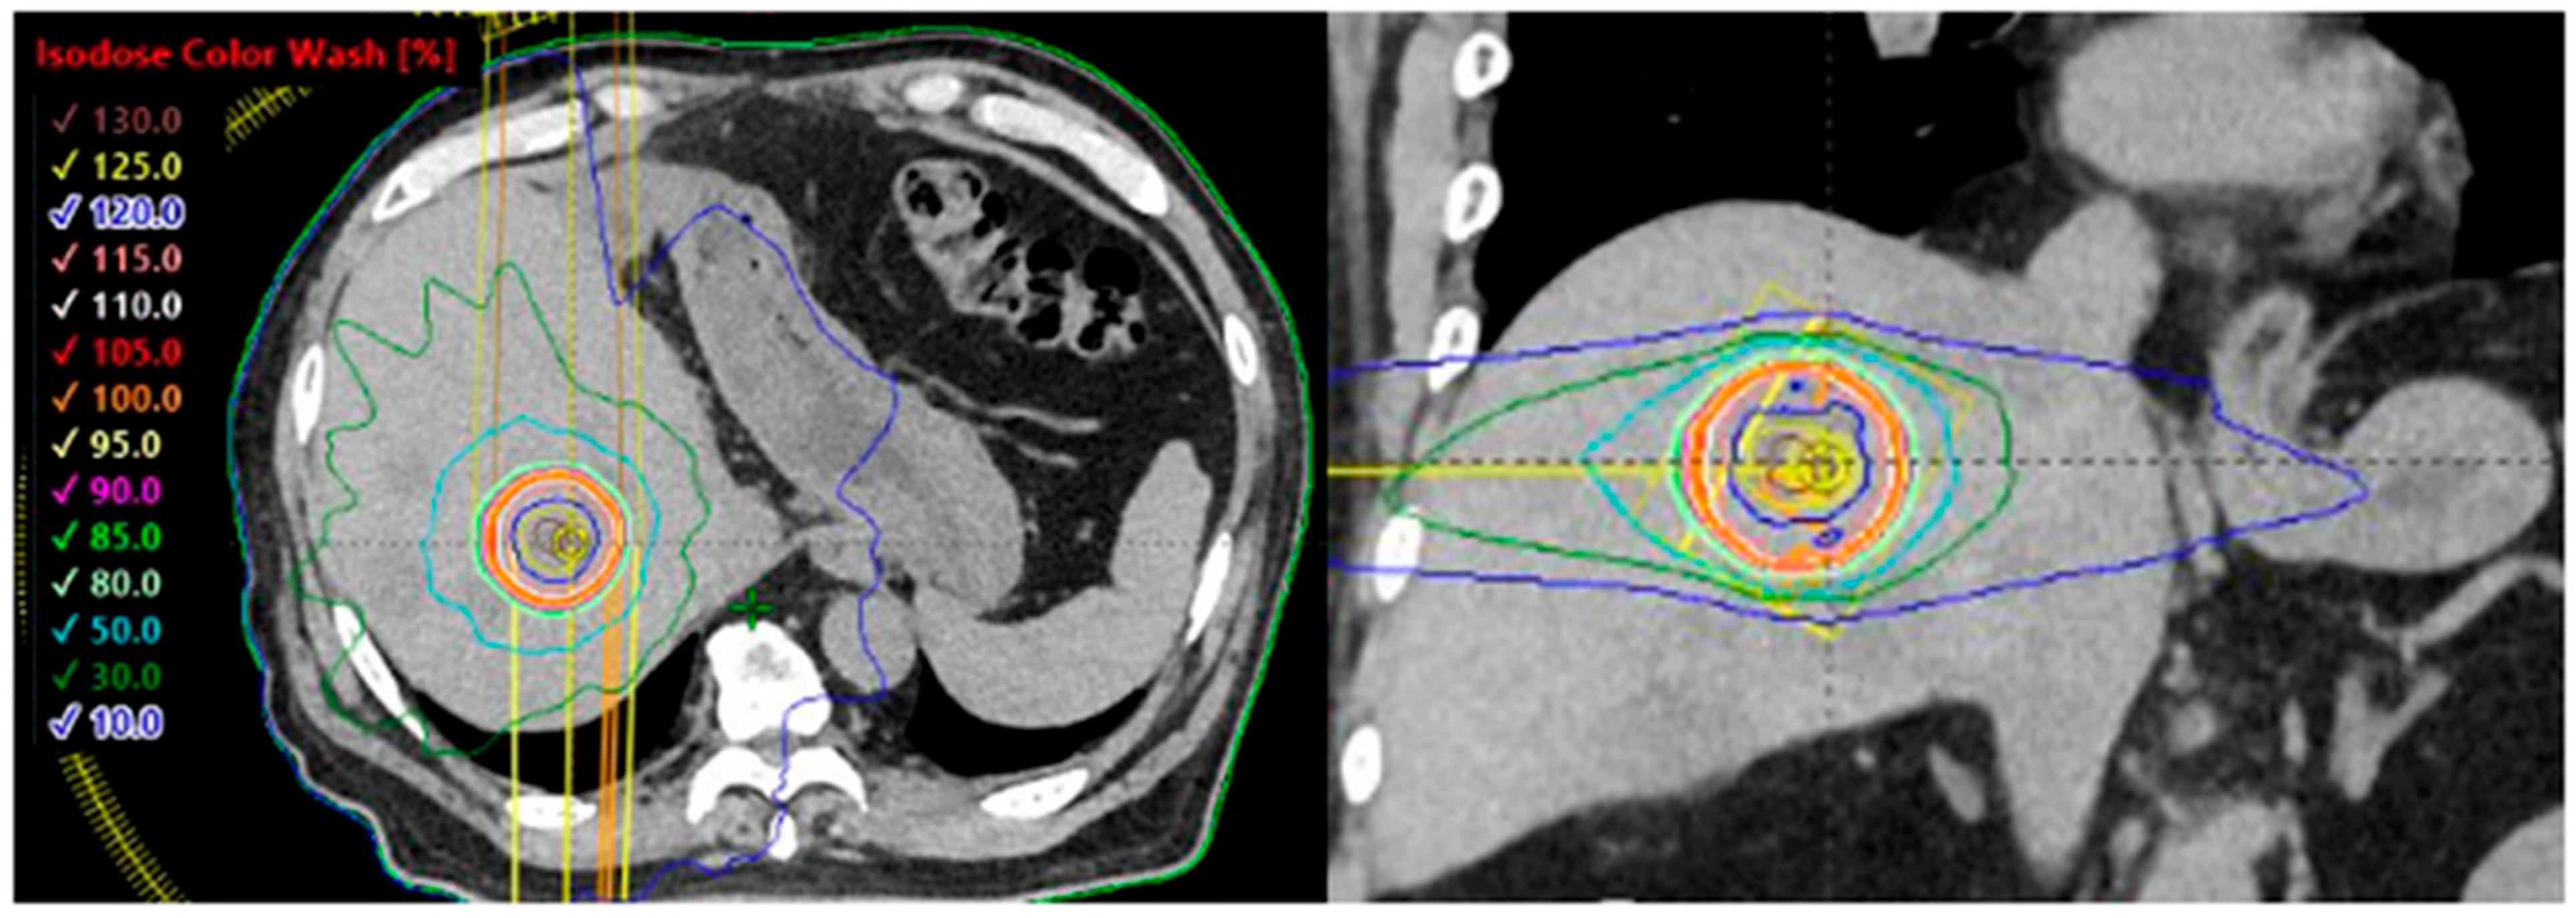

4. Liver Oligometastases of Lung Cancer